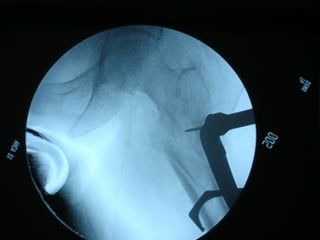

Tc pre op

Rx post